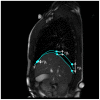

are computed as vertical subtraction of caudal from cranial diaphragm position. The three parameters correspond to the anterior (

), middle (

) and posterior (

) diaphragm part. Points were spread evenly on the diaphragm contour with small constant drift of

and

from the contour margins.